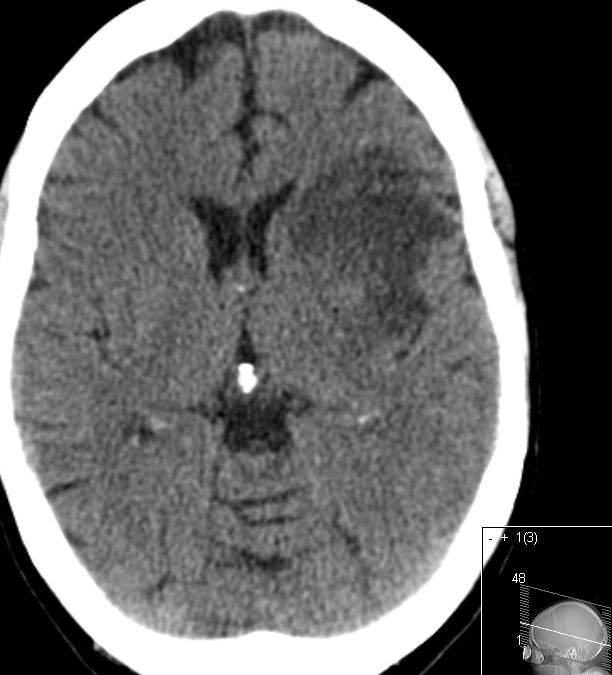

Dünnschicht-CT Ausschluss Blutung, Bestimmung der Thrombuslänge

ASPECTS Alberta Stroke Program Early CT Score (1,2) CT-Bewertungsscore bei akutem, ischämischem Apoplex der ACM Beurteilung von 10 Regionen:

M1–M6: Hirnrinde,

C: Nucleus caudatus

L: Nucleus lentiformis, Putamen

IC: Capsula interna

I: Inselregion

Keine Veränderung im CT: 10 Punkte

für jede veränderte Region ein Punktabzug

ACI-Verschluß 63-jährige Frau, die wegen TIA eingeliefert wurde. Daraus entwickelte sich eine komplette Halbseitensymptomatik. Das CT zeigt einen Abgangsverschluss der linke ACI.

CT-Angio

Gut markierter Media-Infarkt